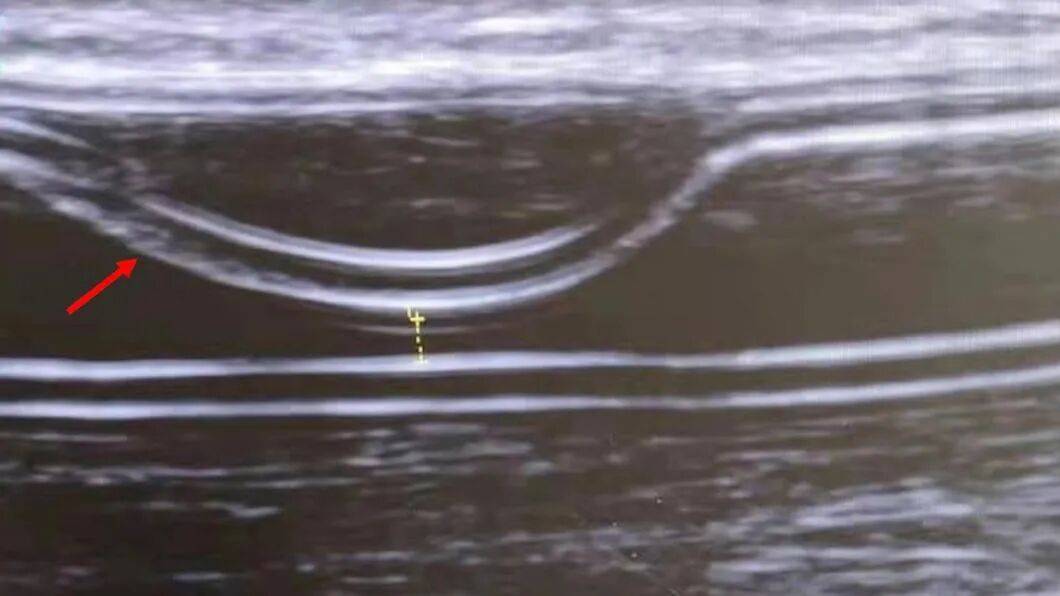

圖3:即穿型人工血管夾層超聲圖

本研究對即穿型人工血管夾層的特點與處理最新研究進展進行了綜述論文。作者在PubMed 資料庫中進行檢索,共發現7 例病例報告和 1 項佇列研究,對其進行總結分析後發現:(1)早期插管動靜脈移植物夾層的診斷主要依靠多普勒超聲檢查。(2)大多數報道的病例涉及 Acuseal 移植物,夾層主要位於中膜和外膜之間,且多在前壁。其可能與球囊擴張、血管鞘插入、不適當的穿刺角度以及反覆的關節活動有關。(3)目前尚無標準的治療方案。可用的治療選擇包括經皮腔內血管成形術、支架植入、移植物置換和保守觀察。移植物置換的初始通暢率最佳,其次為支架植入。建議將支架植入或移植物置換作為一線治療方法。